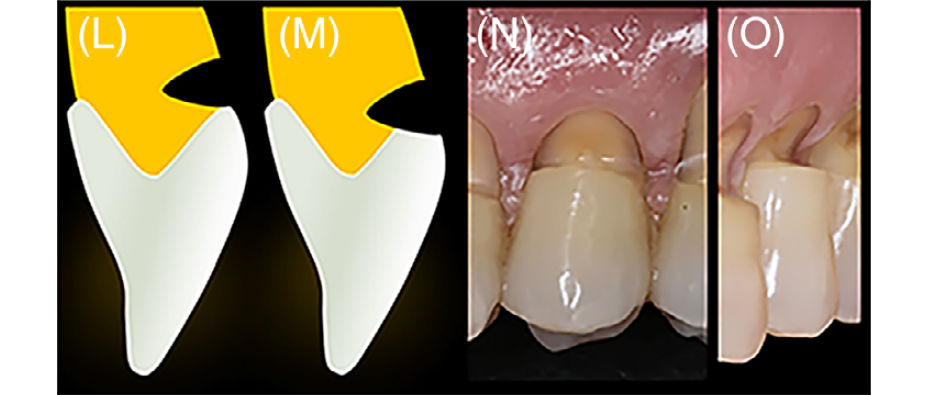

Вид V-образных поражений: A+ (L) и B+ (M).

Рис 1 (L-O). Алгоритм принятия решений при лечении некариозных пришеечных поражений (NCCLs) в комбинированных дефектах (CDs). (L–O) Вид V-образных поражений: A+ (L) и B+ (M). V-образные NCCL обычно характеризуются значительной вестибуло-пульпарной глубиной при ограниченной апико-коронковой высоте, часто с соотношением глубины к высоте, близким к 1. В случаях A+ или B+ V-образных дефектов следует рассматривать полную реставрацию NCCL для сохранения тканей зуба и формирования более благоприятного, гармоничного профиля выхода

Алгоритм принятия решений при лечении рецессионного компонента в комбинированных дефектах

Рис 6. Алгоритм принятия решений при лечении рецессионного компонента в комбинированных дефектах (CD).

(Слева) При отсутствии кератинизированной ткани (KT) или при KT < 2,0мм и толщине десны (GT) < 0,8мм соединительнотканный трансплантат (CTG) обязателен, поскольку это единственный метод, позволяющий увеличить GT до 1,5мм и одновременно увеличить KT

(Середина) При 0,8 < GT < 1,5мм необходимо улучшение GT до уровня около 1,5мм. В данной ситуации может быть использован либо тонкий CTG, либо мягкотканный заместитель

(Справа) При GT ≥ 1,5мм возможна тактика без трансплантации